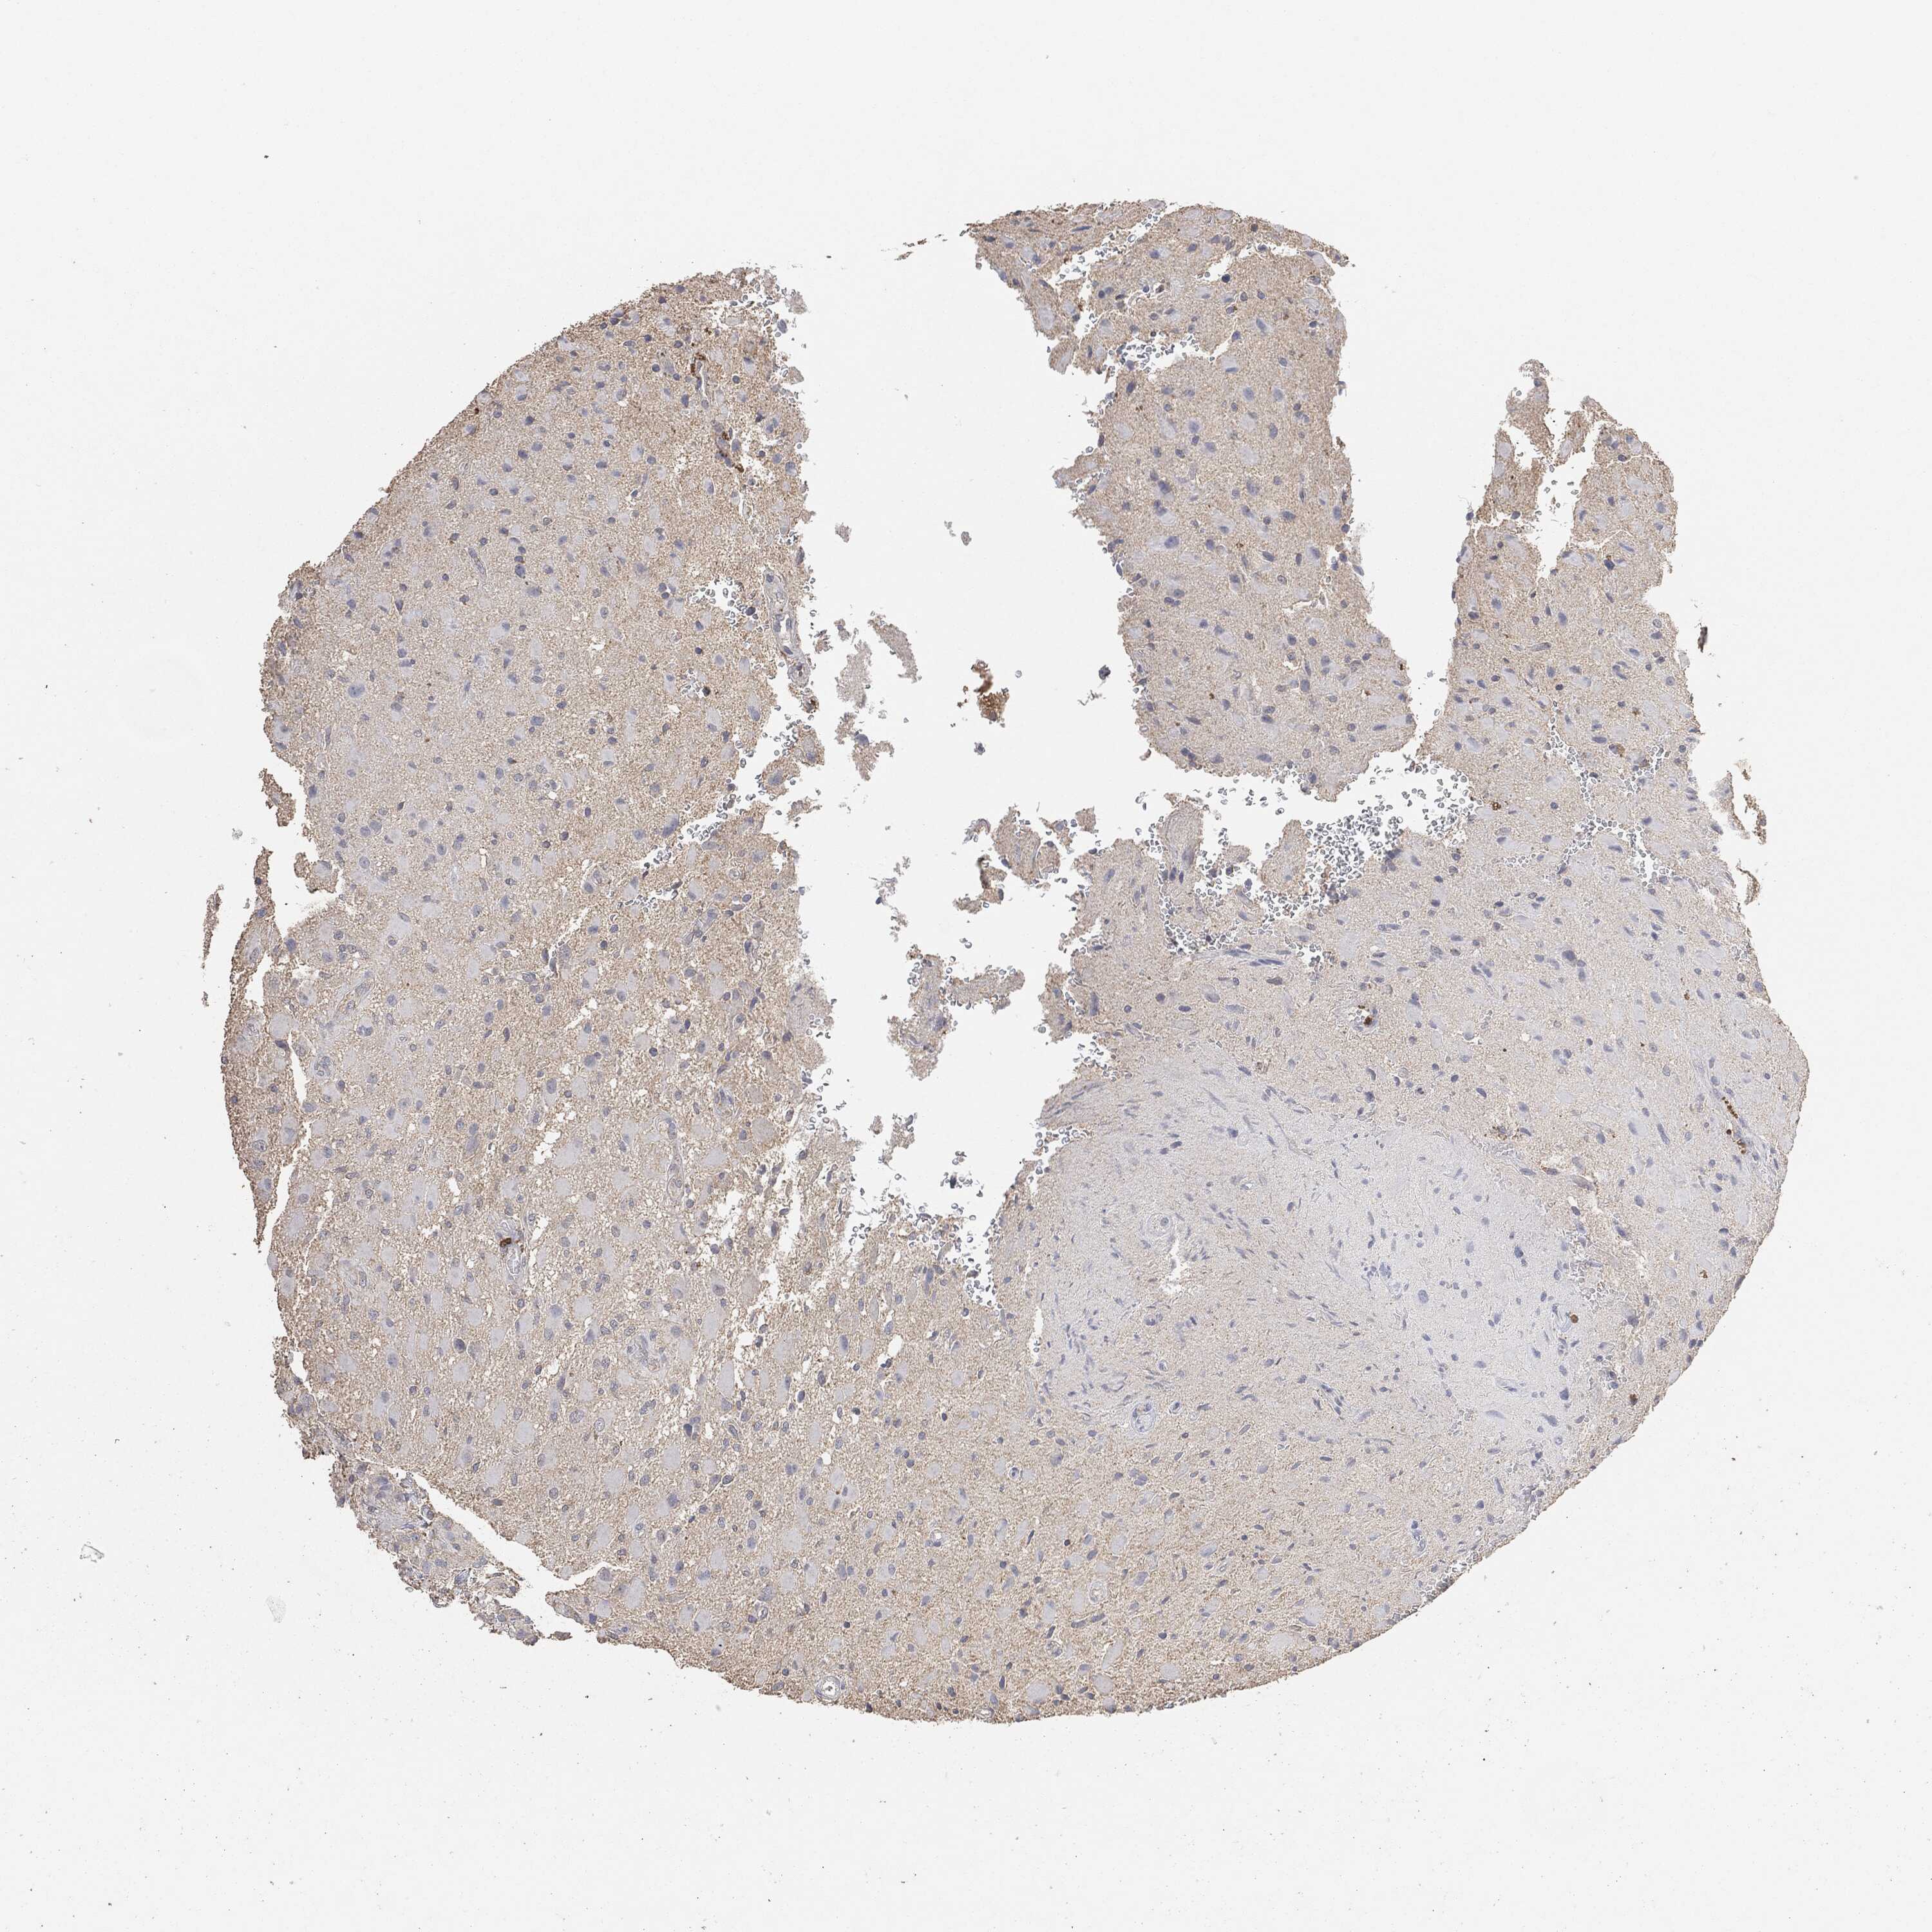

GLIOMA - Protein expressioni

A mouse-over function shows sample information and annotation data. Click on an image to view it in a full screen mode. Samples can be filtered based on level of antibody staining by selecting one or several of the following categories: high, medium, low and not detected. The assay and annotation is described here.

Note that samples used for immunohistochemistry by the Human Protein Atlas do not correspond to samples in the TCGA dataset.

Antibody stainingi

Antibody staining in the annotated cell types in the current human tissue is reported as not detected, low, medium, or high, based on conventional immunohistochemistry profiling in selected tissues. This score is based on the combination of the staining intensity and fraction of stained cells.

Each image is clickable and will lead to virtual microscopy that enables deeper exploration of all samples and also displays staining intensity scores, fraction scores and subcellular localization as well as patient and tissue information for each sample.

Glioma, malignant, High grade

Glioma, malignant, Low grade

Glioma, malignant, NOS